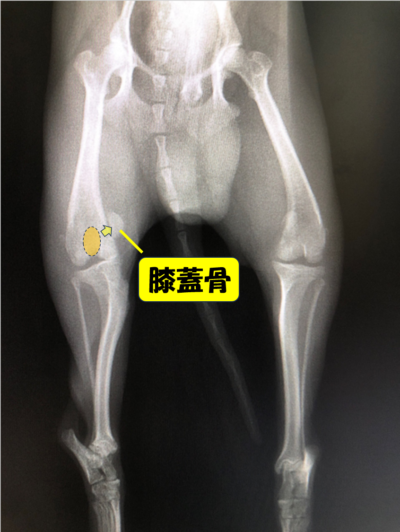

膝蓋骨脱臼(通称パテラ)とは、本来は膝蓋骨(膝のお皿の骨)が大腿骨(太ももの骨)の真正面になければいけないのに、膝蓋骨が脱臼してしまう病気です。

内側にずれてしまうことを内方脱臼、外側にずれてしまうことを外方脱臼といいます。

診断

・レントゲン検査